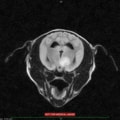

正常な脳室

拡張した脳室